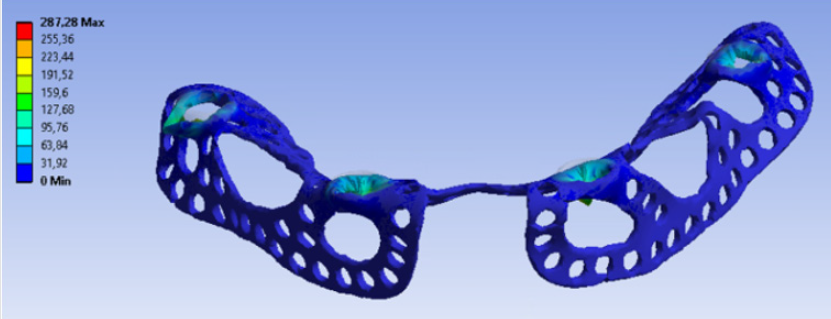

Distant forces were used as they would normally act on the implant from the dental crown. We used data obtained from scientific literature according to which magnitude occlusal forces can be between 100 and 800 N. In the first analysis, maximum 800 N occlusal force was defined. Its result is presented in Figure 7 It is notable that stresses only raised at the acting point of the force. Stress intensity was 287.28 MPa for maximum occlusal load. Another scenario was also investigated in which the frontal part of the implant was loaded with the lowest, while the back of the implant was loaded with the highest occlusal forces. Figure 8 presents the results of this loading scenario with the maximum stress level of 207.6 MPa. It is notable in this case that highest stresses raised at the back of the implant at the acting points of the forces. Different force variations were all analysed from minimum to maximum loads. Figure 9 shows the set of completely linear results. Highest stress intensity was 287.28 MPa for maximum occlusal forces. The studied implant was inserted after manufacturing. Implant fitting to the bone ridge of the patient can be seen in Figure 10.

In our mechanical analyses, the highest stress intensity was 278.28 MPa for maximum occlusal load. Yield strength of Grade 23 Ti-6Al-4V alloy is 760MPa, which means if we calculate maximum permissible stress with the safety factor of 2, the structure will still be safe. Volume reduction was successful. Consequently, the mass of implanted titanium alloy was reduced in the patient. Further studies will be conducted to further decrease the amount of titanium material.